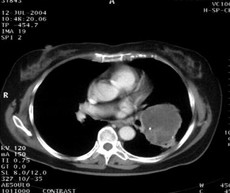

女,62岁。右大腿滑膜肉瘤,术后左下肺转移,9.5×7.5cm。CT引导下瘤内注射今又生,1×1012VP/次/周,共8次,结合60Gy放射照射。治疗后肿瘤缩小48%,CT示瘤内低密度区占50%以上,即肿瘤大部分坏死。

治疗后